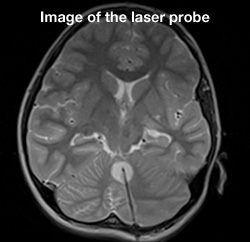

Laser ablation brain surgery

On May 29, 2013, Cook Children's became the first pediatric hospital in North Texas to perform iMRI-guided laser ablation brain surgery. For the patient, it was a triple win. He was the first to undergo this surgery, and the first at Cook Children's to have this surgery for epilepsy. But the biggest win of all was that just 24 hours after the surgery, the patient was seizure-free and discharged from the hospital. Being the first to perform this surgery wasn't the only benchmark we set that day. We raised the bar on more effective treatment for kids with epilepsy and brain tumors.

Thanks to this minimally invasive surgery, children, teens and young adults no longer have to undergo a craniotomy, or open brain surgery, for certain types of epileptic lesion or brain tumor procedures. And because tumors and lesions are removed by laser without cutting, the level of risk is greatly minimized and the positive benefits of surgery are greatly maximized. Best of all, because the surgery is so minimally invasive, patients can often return home within one to two days of their surgery. Recovery time can also be shortened so that ultimately the kids we treat can get back to business of being kids.

Currently, only 10 pediatric facilities in the U.S. offer this amazing surgery. Also known as stereotactic laser ablation, this iMRI-guided, minimally invasive procedure allows abnormal tissue to be thermally destroyed in real time. The surgery takes place in our iMRI suite, which reduces patient's surgery and anesthesia time and allows for targeted abnormal tissue removal, with little to no risk to surrounding brain tissue. Most patients go home within 24 hours and with only one stitch.

What is laser ablation?

Brain surgery is challenging, and some conditions are more difficult than others. At Cook Children's, we are constantly seeking the most advanced solutions to these obstacles, so we can focus on the most important thing, your child's well-being. Brain tumors and lesions pose a special risk, especially those that are deep in the brain or surrounded by very delicate tissue. For those patients at the highest risk, laser ablation helps the neurosurgeons at Cook Children's precisely target tumors and lesions while reducing, and even eliminating, damage to surrounding brain tissue.

Laser ablation uses targeted light energy to destroy tumors and damaged tissue. Using guided iMRI technology, the doctors can see precisely where the tumor or lesion is in the brain and the laser energy can then be delivered right to the targeted area.

• A 3.2mm hole is drilled for cranial access.

• The patient is placed into the iMRI.

• The surgeon guides the laser into position using imaging and then thermally destroys the abnormal tissue.

• The laser applicator is removed and a stitch is placed to close the incision.